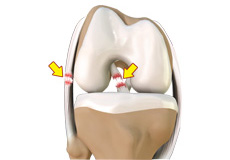

Articular Cartilage and Menisci of the Knee

Movement of the bones causes friction between the articulating surfaces. To reduce this friction, all articulating surfaces involved in the movement are covered with a white, shiny, slippery layer called articular cartilage. The articulating surface of the femoral condyles, tibial plateaus and the back of the patella are covered with this cartilage. The cartilage provides a smooth surface that facilitates easy movement.

To further reduce friction between the articulating surfaces of the bones, the knee joint is lined by a synovial membrane that produces a thick clear fluid called synovial fluid. This fluid lubricates and nourishes the cartilage and bones inside the joint capsule.

Within the knee joint, between the femur and tibia, are two C-shaped cartilaginous structures called menisci. Menisci function to provide stability to the knee by spreading the weight of the upper body across the whole surface of the tibial plateau. The menisci help in load-bearing i.e. it prevents the weight from concentrating onto a small area, which could damage the articular cartilage. The menisci also act as a cushion between the femur and tibia by absorbing the shock produced by activities such as walking, running and jumping.